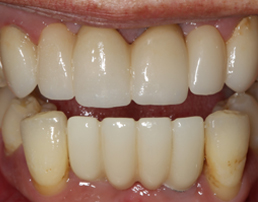

CROWN FITTED

Card image Actual Practice Photographs ©Dr.Pavan Bopanna

IMPLANT SUPPORTED BRIDGE